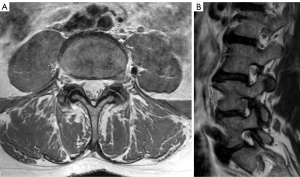

Patients were anaesthetised (general anaesthetic) and placed prone on a Wilson frame or Jackson table or equivalent. A preoperative fluoroscopic level check was performed, and the midline was marked. An example of a left L4/5 FLDH is shown in Figure 1 via axial (Figure 1A) and sagittal (Figure 1B) T2-weighted magnetic resonance imaging (MRI) images. Depending on the level, a paramedian incision of approximately 4 cm length was marked in the range of 2.5–4.5 cm from the midline. For example, 2.5 cm at L2/3, 3 cm at L3/4, 3.5 cm at L4/5 and 4 cm at L5/S1. Adjustments were made depending on patient weight, musculature, fat distribution and with reference to the preoperative MRI measurements from the midline to the outer edge of the superior articular process (SAP) of the caudal vertebra. Often, we added 0.5 cm to these measurements due to thickness of fat above lumbar fascia.